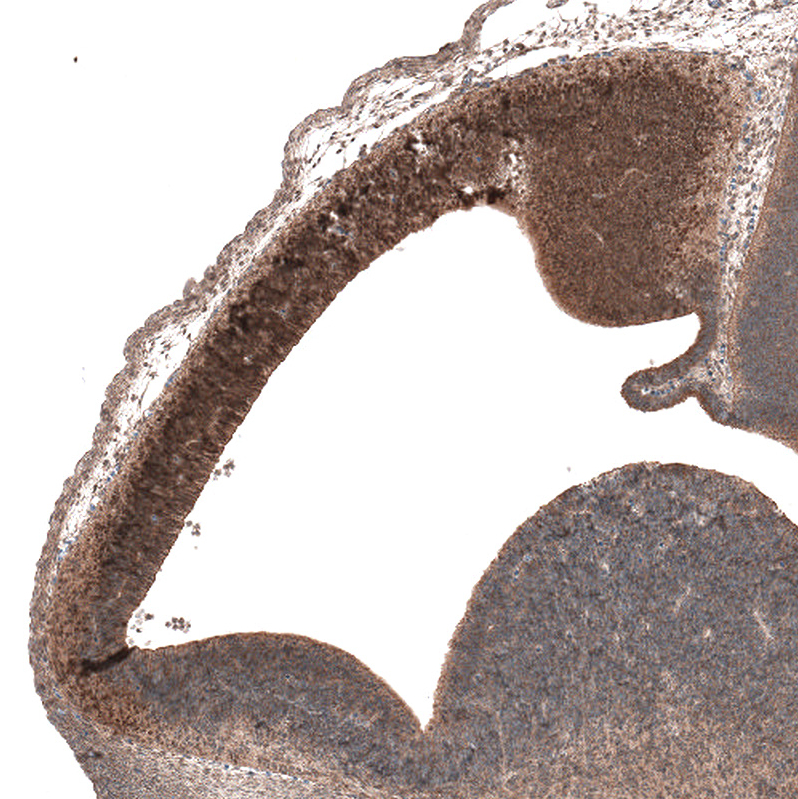

Immunohistochemical staining of human kidney shows moderate nuclear positivity in cells in a subset of renal tubules.